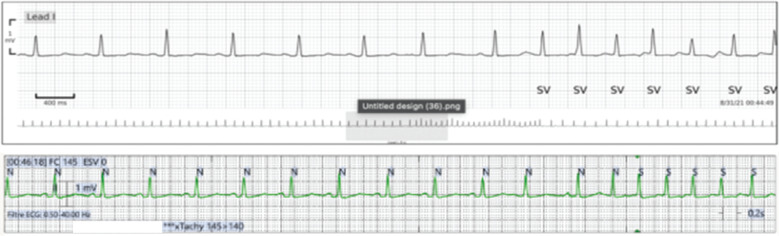

Telemetry monitoring (conventional cardiac monitoring system [CCMS]) is a universal method for postoperative arrhythmia detection; however, the clinical challenge of alarm fatigue, primarily associated with noise or cable disconnections, persists. The introduction of wireless continuous cardiac monitoring (WCCM) represents a potential solution to enhance recording fidelity. Patients were simultaneously outfitted with both a monitoring device considered the standard of care and a novel adhesive wireless patch. A 48-h cardiac monitoring session with the two devices occurred after cardiac surgery in a unit equipped with a telemetry system. A total of 53 patients with a mean age of 60 ± 17 years were included in the trial. The number of events detected by the two systems was significantly different at 190 versus 174 for the CCMS and the WCCM system, respectively (P < .05). However, the percentage of agreement was not significantly different at 91% versus 88% (P = .37). Events were classified as follows: pause (2 events, 1%), atrial or premature ventricular contractions (18 events, 11%), atrial flutter or fibrillation (76 events, 45%), bradycardia (12 events, 7%), and tachycardia (61 events, 36%). False alarms were significantly more frequent with the CCMS (n = 21) than with the WCCM system (n = 5; P = .002). The study successfully demonstrated the feasibility and usability of wireless monitoring for patients requiring telemetry. The overall results are compelling, as the WCCM system performed satisfactorily, achieving results comparable to those obtained with the CCMS, even with significantly fewer false alarms.